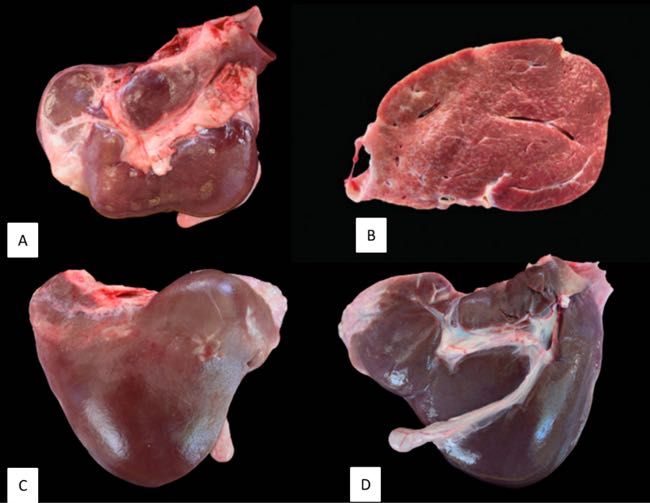

Gross hepatic lesions were present in five of six animals. Two sheep showed atrophy and fibrosis of the left lobe. Three animals had marked liver atrophy with a firm, smooth, kidney-shaped appearance, consistent with severe interstitial fibrosis. In these cases, the gallbladder was also reduced and fibrotic, appearing as a dorsally displaced cord (Figure 5).

Figure 5. Hepatic gross lesions. A. Hepatic atrophy and fibrosis. B. Severely affected liver with interstitial fibrosis with band-like arrangement. C and D. Both sides of the same liver show a rounded surface, atrophy of the caudate lobe, increased size of the right and quadrate lobes and the presence of the gallbladder reduced and fibrosed, remaining only as a cord that has been displaced dorsally.

Microscopically, livers without evident gross lesions also showed periportal inflammation and fibrosis. Overall, the livers exhibited moderate-to-severe portal and bridging fibrosis, bile duct hyperplasia and scattered foci of hepatocellular necrosis. Vascular lesions were evident in vessels accompanying interlobular bile ducts, with severity paralleling the gross hepatic changes. Intimal proliferation with fibrosis and increased elastic fibres affected arteries and veins, mainly in interlobular areas, with fragmented elastic fibres admixed with collagen and mild mononuclear infiltration. In the gallbladder, lesions consisted of patchy epithelial necrosis/denudation, multifocal mucous gland proliferation, and fibrosis of the muscular and adventitial layers. No vascular lesions comparable to those in the liver were identified (De las Heras et al., 2022).